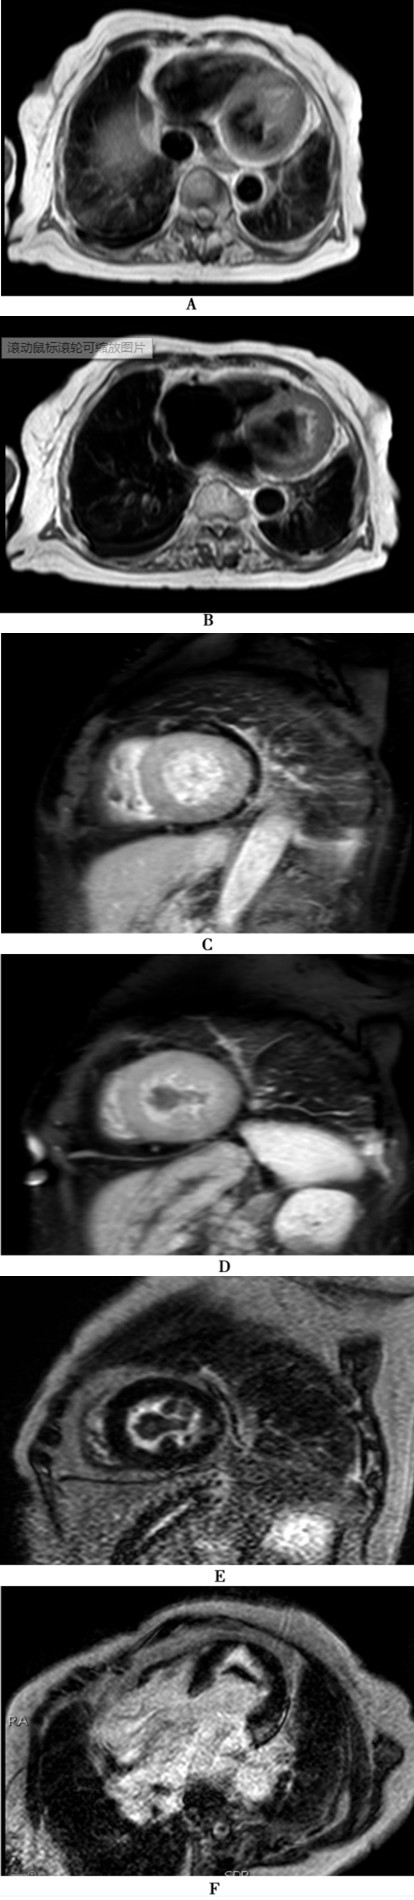

图12-3 心脏磁共振

A、B:平扫T1加权成像示左心室心内膜增厚,左心室心尖部闭塞,左心室腔内见短T1异常信号影附着于心尖部;C:早期增强图像,左心室短轴位显示左心室心腔中部对比及充盈良好;D:早期增强图像,左心室短轴位显示心尖部团块状充盈缺损;E:延迟增强图像,左心室短轴位显示左心室腔内病灶无延迟强化,左心室中部外侧壁见片状强化;F:延迟增强图像,四腔心位显示左心室心尖部病灶无延迟增强,左心室基底部外侧壁见片状延迟强化

3月29日,心脏磁共振成像平扫+增强:平扫示左心房、右心房、左心室增大,右心室结构正常,左心室心内膜增厚、心尖部闭塞,左心室可见团块状软组织影附着在心尖部,呈短T 1、长T 2异常信号,心肌内未见异常信号;左心室舒张受限,收缩功能减弱,二尖瓣、三尖瓣反流;增强扫描示左心室心内膜明显强化,左心室内病灶未见强化;灌注扫描心室壁未见灌注缺损;延迟扫描示左心室游离壁可见多发斑片状延迟强化;双侧少量胸腔积液(图12-3)。诊断:考虑限制型心肌病,左心室心尖部附壁血栓形成,二尖瓣、三尖瓣反流,左心功能减弱;双侧胸腔少量积液。

1.如何甄别限制型心肌病患者的增厚心内膜与附壁血栓?

该患者于3月22日所行超声心动图提示附壁血栓后启用低分子肝素、华法林抗凝治疗,4月8日复查超声心动图发现左心室心尖部 “附壁血栓”体积、范围较前缩小,提示抗凝治疗见成效,但 “附壁血栓”范围仍然很大,而且 “附壁血栓”的致密度与3月22日所描述的 “质感松软”不一致,由此质疑左心室心尖部异常回声到底是否全部为血栓形成?超声心动图医生再次审慎观察左心室心尖部低回声征象,最终发现经过17天的抗凝治疗后,原来左室心尖的附壁血栓已消失,现在所观察到的左心室心尖部异常回声是异常增厚的心内膜。与患者3月26日的心脏MRI图像比较,发现磁共振示左心室心尖部心内膜异常增厚,而心尖部病灶无强化。最终明确该患者在左室心内膜增厚的同时伴附壁血栓形成。